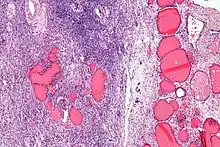

Micrograph of a struma ovarii. Characteristic thyroid follicles are seen on the right, and ovarian stroma on the left. H&E stain.

A struma ovarii (literally: goitre of the ovary) is a rare form of monodermal teratoma that contains mostly thyroid tissue, which may cause hyperthyroidism.[1]